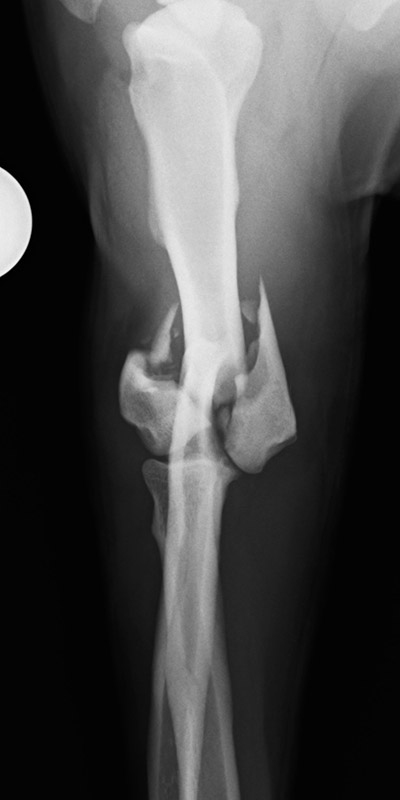

肘関節内骨折

アメリカン・コッカー・スパニエル(5歳)

車の窓から落下

手術前

手術後